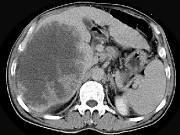

问题 男,62岁,右上腹痛半年,腹部包块,黄疸较重,AFP阴性,CT检查如图,最可能的诊断为()

选项 A.原发性肝癌 B.胆管上皮癌 C.肝囊肿 D.肝脓肿 E.肝错构瘤

答案 B